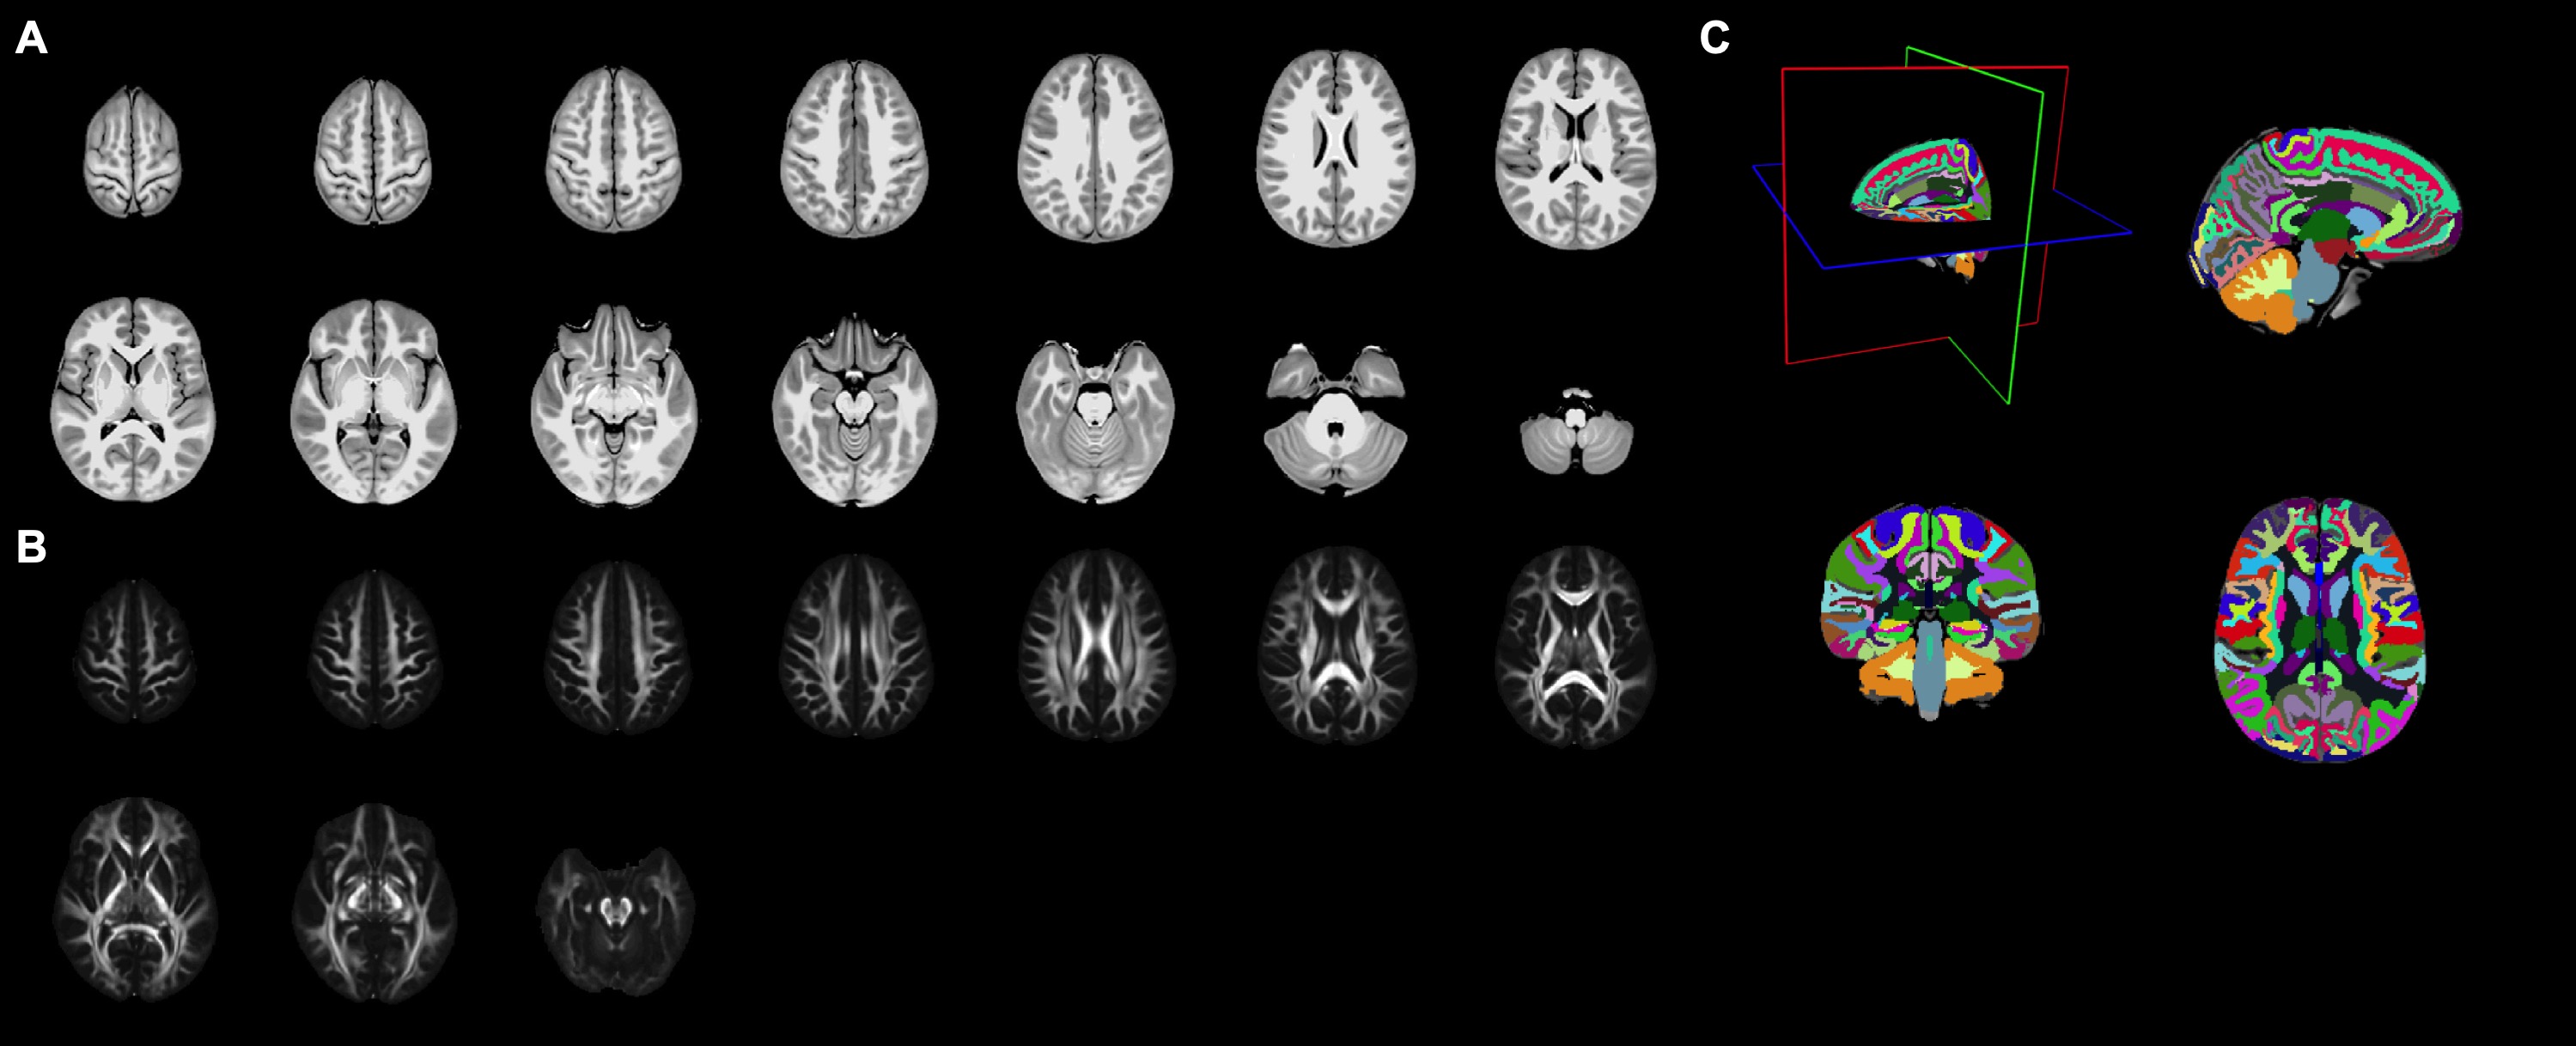

Figure 2. Illustrations of the population-specific brain atlas, including the T1 (A) and DTI (B) templates in axial views, and the semantic labels of cortical and white matter parcellations (C).